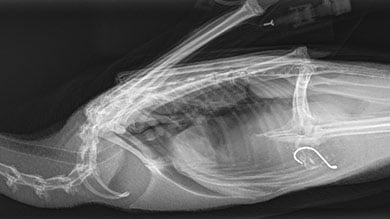

Pūteketeke with fishhook x-ray

Image: Wildlife Hospital Dunedin

Wildlife Hospital Dunedin Director and Senior Wildlife Veterinarian Dr Lisa Argilla says removing foreign bodies, in particular fishhooks, is a major procedure which involves abdominal surgery to access the stomach to remove the item.

Fishhooks also risk perforating the stomach and causing peritonitis (serious infection around the internal organs) because of how sharp they are.